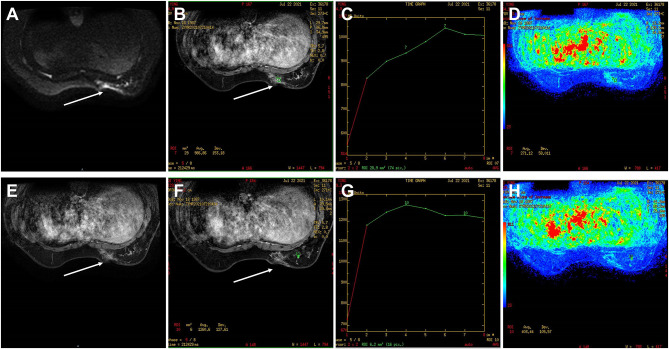

Epithelial-myoepithelial carcinoma (EMC) of the breast is a rare biphasic tumor composed of intermixed malignant epithelial and myoepithelial components. Breast epithelial myoepithelial carcinoma lacks therapeutic strategies due to its rarity, and currently local treatment is still the main treatment. Herein we report an epithelial-myoepithelial carcinoma of the breast in a 33-year-old woman undergoing breast conserving surgery, sentinel lymph node biopsy, adjuvant chemotherapy and radiotherapy, with rapid liver and lung metastasis. After radiofrequency ablation therapy for metastatic lesions, vinorelbine plus cisplatin and TROP2 antibody-drug conjugate (ADC) treatment were given successively. After a brief improvement, drug resistance developed and the disease progressed. The patient died with the PFS 5.6 months.